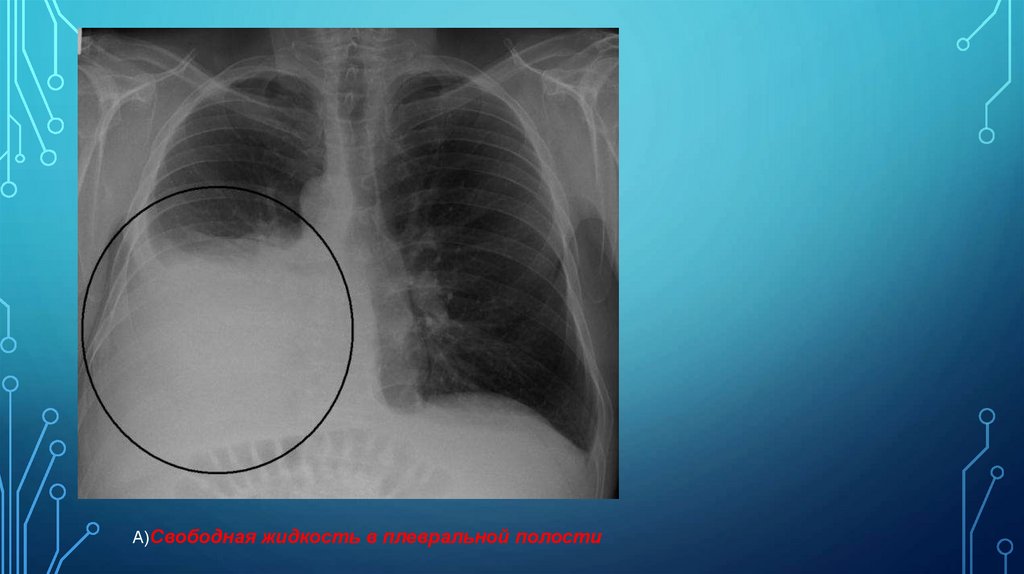

А)Свободная жидкость в плевральной полости в прямой проекции при

вертикальном положении больного проявляется однородным затененим нижне-латеральной

части легочного поля с косой верхней границей (линия Эллиса-Дамуазо), контур ее нечеткий,

при вдохе смещается вниз, при выдохе – вверх